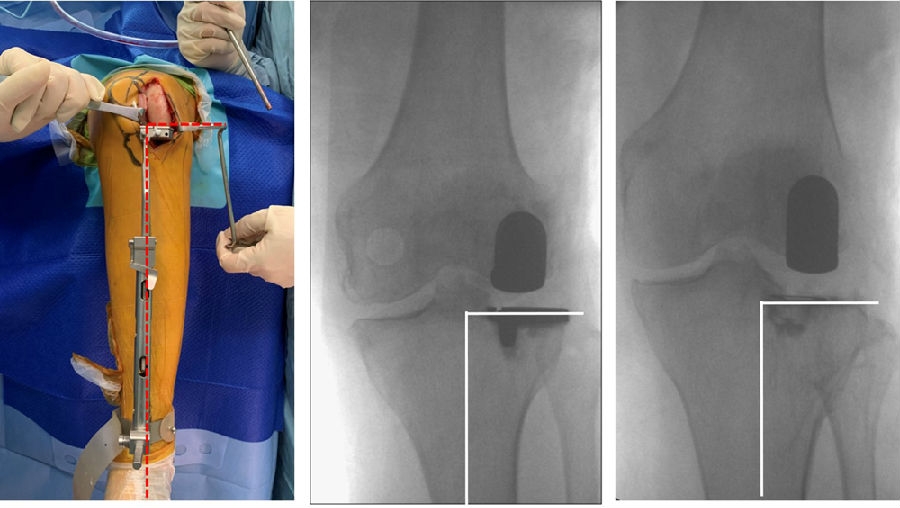

上示图片显示胫骨矢状切面锯切内旋转10-15°。

内旋截骨时,插入髓内导针,将膝关节屈曲45°,此时髌韧带松弛,直视下进行内旋10-15°锯切。

术前动力位片

术前透视。A.模拟负重位B.内翻应力位C.外翻应力位D.侧位